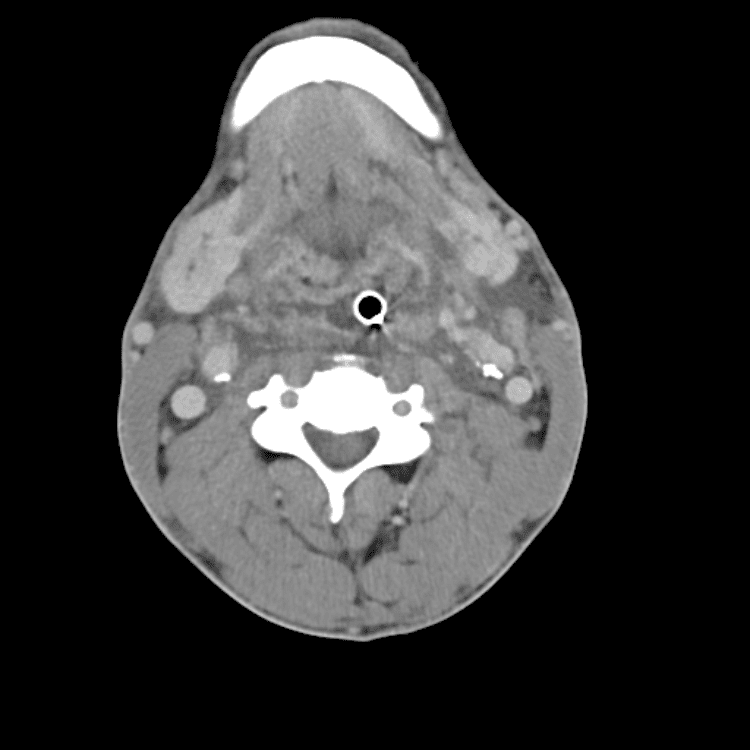

Head and Neck

Simulates call by including subtle or difficult cases and some normals.

27 cases